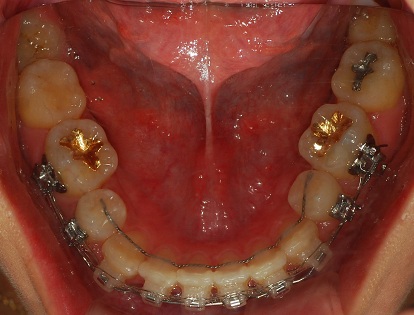

그리고 하악에 치아 배열을 유지하기 위해서 철사를

붙였습니다.

하악사진

철사 붙인거 보이시죠?

저부분 양치를 주의 깊게 잘 해주어야 해요